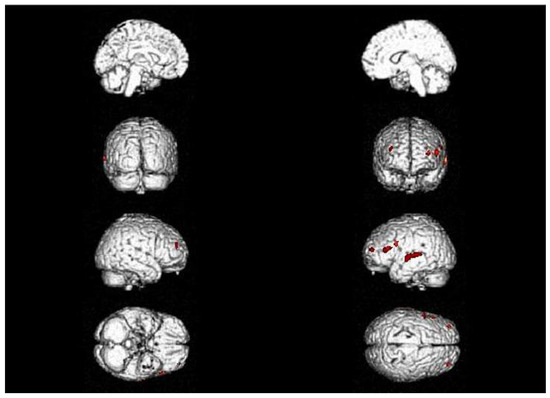

| 2017 | Neurological assessment Neuropsychological assessment (WAIS-IV) Speech therapist assessment Amyloid PET | Mild isolated motor speech disorder No abnormal β-amyloid deposits |